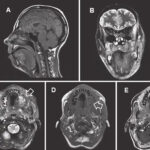

MRI Face With Contrast is an advanced imaging technique which uses powerful magnetic fields and contrast dyes to provide clear images of facial structure. It is highly useful in diagnosing soft tissues, nerves, muscles, and blood vessels of the face. The test is often performed as a diagnostic tool in the diagnosis and assessment of a range of clinical conditions including tumor, infection, facial nerve disease, sinus disease, and vascular diseases. By improving the contrast of certain areas, the contrast agent helps to catch slight abnormalities that one may not see when on non-contrast imaging. This is a non-invasive technique. It is safe, painless, and does not use radiation; therefore it is highly preferred for patients who need highly exacting images of the face. With high-resolution images and 3D visualization, MRI Face With Contrast helps in treatment planning, operative guidance, and monitoring progress of facial diseases. Visit Medifyhome, for more information on MRI Face with Contrast.

MRI Face With Contrast uses technologically advanced magnetic resonance imaging in synchronization with an injective contrast dye within the body. The contrast enables better visualization of specific tissues, increasing the detection rate for abnormalities that might include inflammation, tumors, or vascular conditions. It offers excellent depiction of facial structures; among them are: